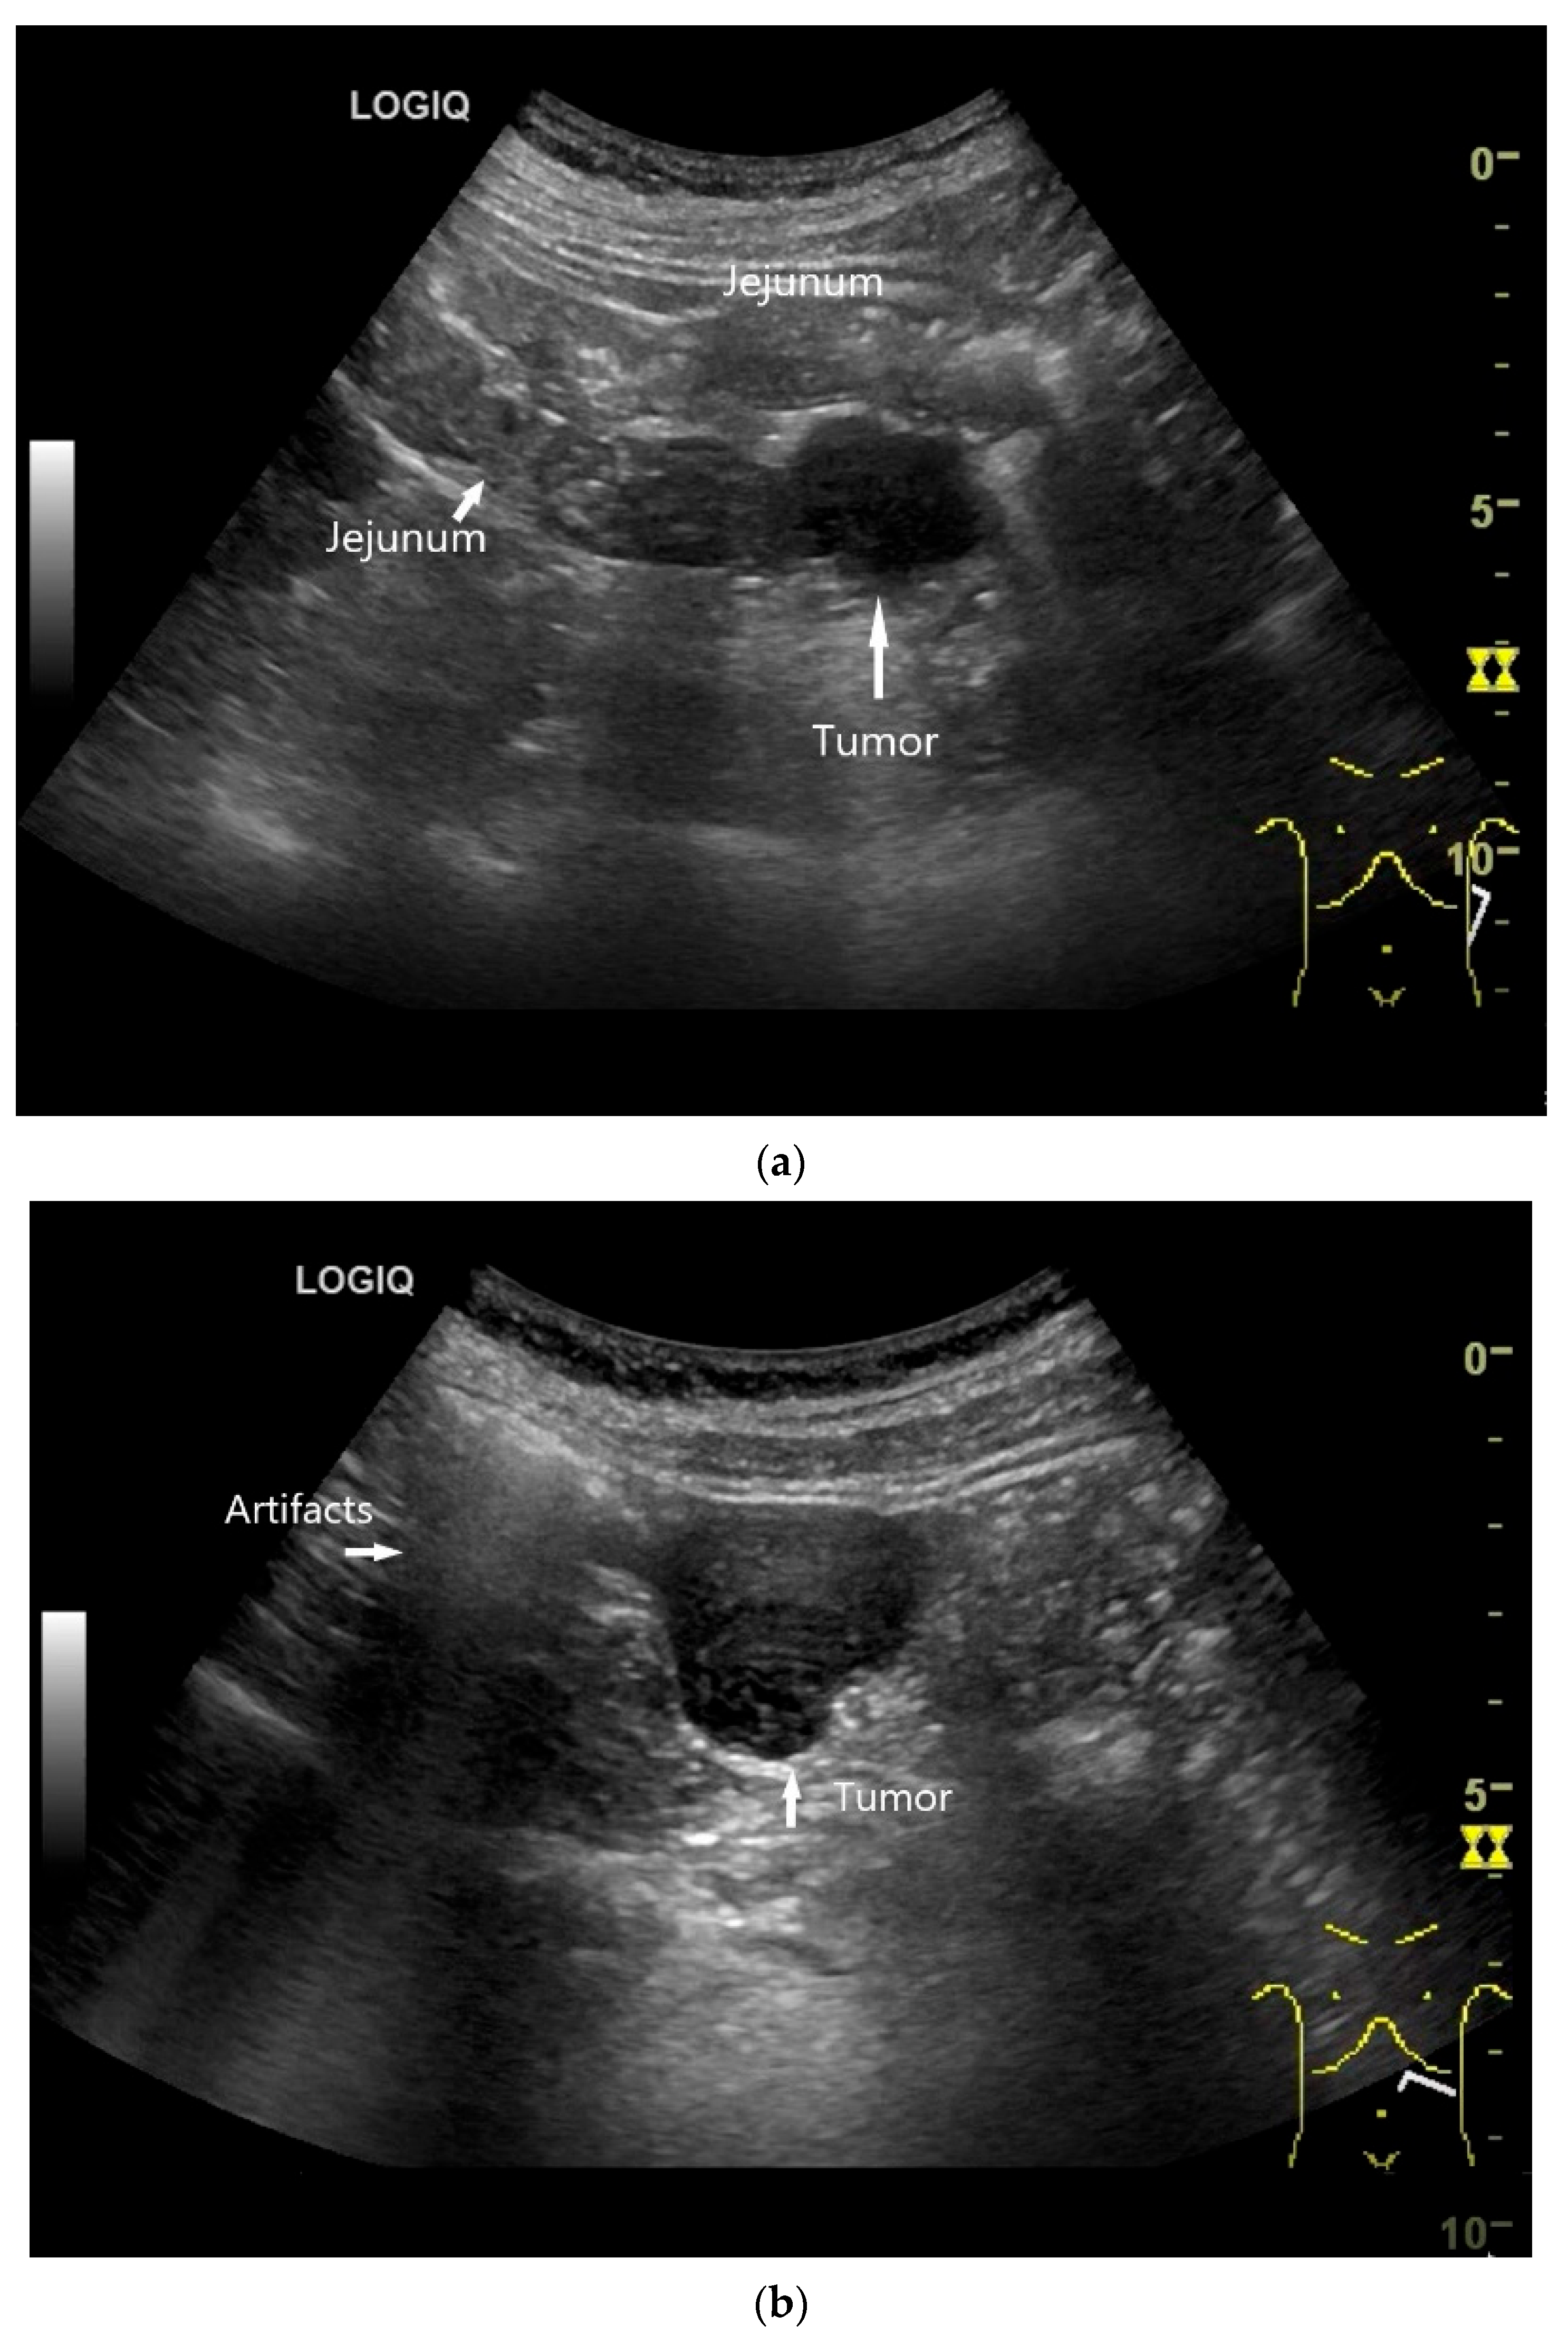

- Wu, S.; Yu, H.; Liu, Y.; Zhou, H.; Zhou, Y. Small bowel adenocarcinoma of the jejunum detected by double contrast enhanced ultrasound: A case report of a novel ultrasound modality. Front. Oncol. 2024, 14, 1288041. [Google Scholar] [CrossRef]

| Neuroendocrine tumor | Small, nodular hypoechoic wall thickenings, mostly in the submucosa with spreading into the other layers. Usually with small vessels on CDI. Regionally enlarged lymph nodes. Multilocular manifestations are possible. |